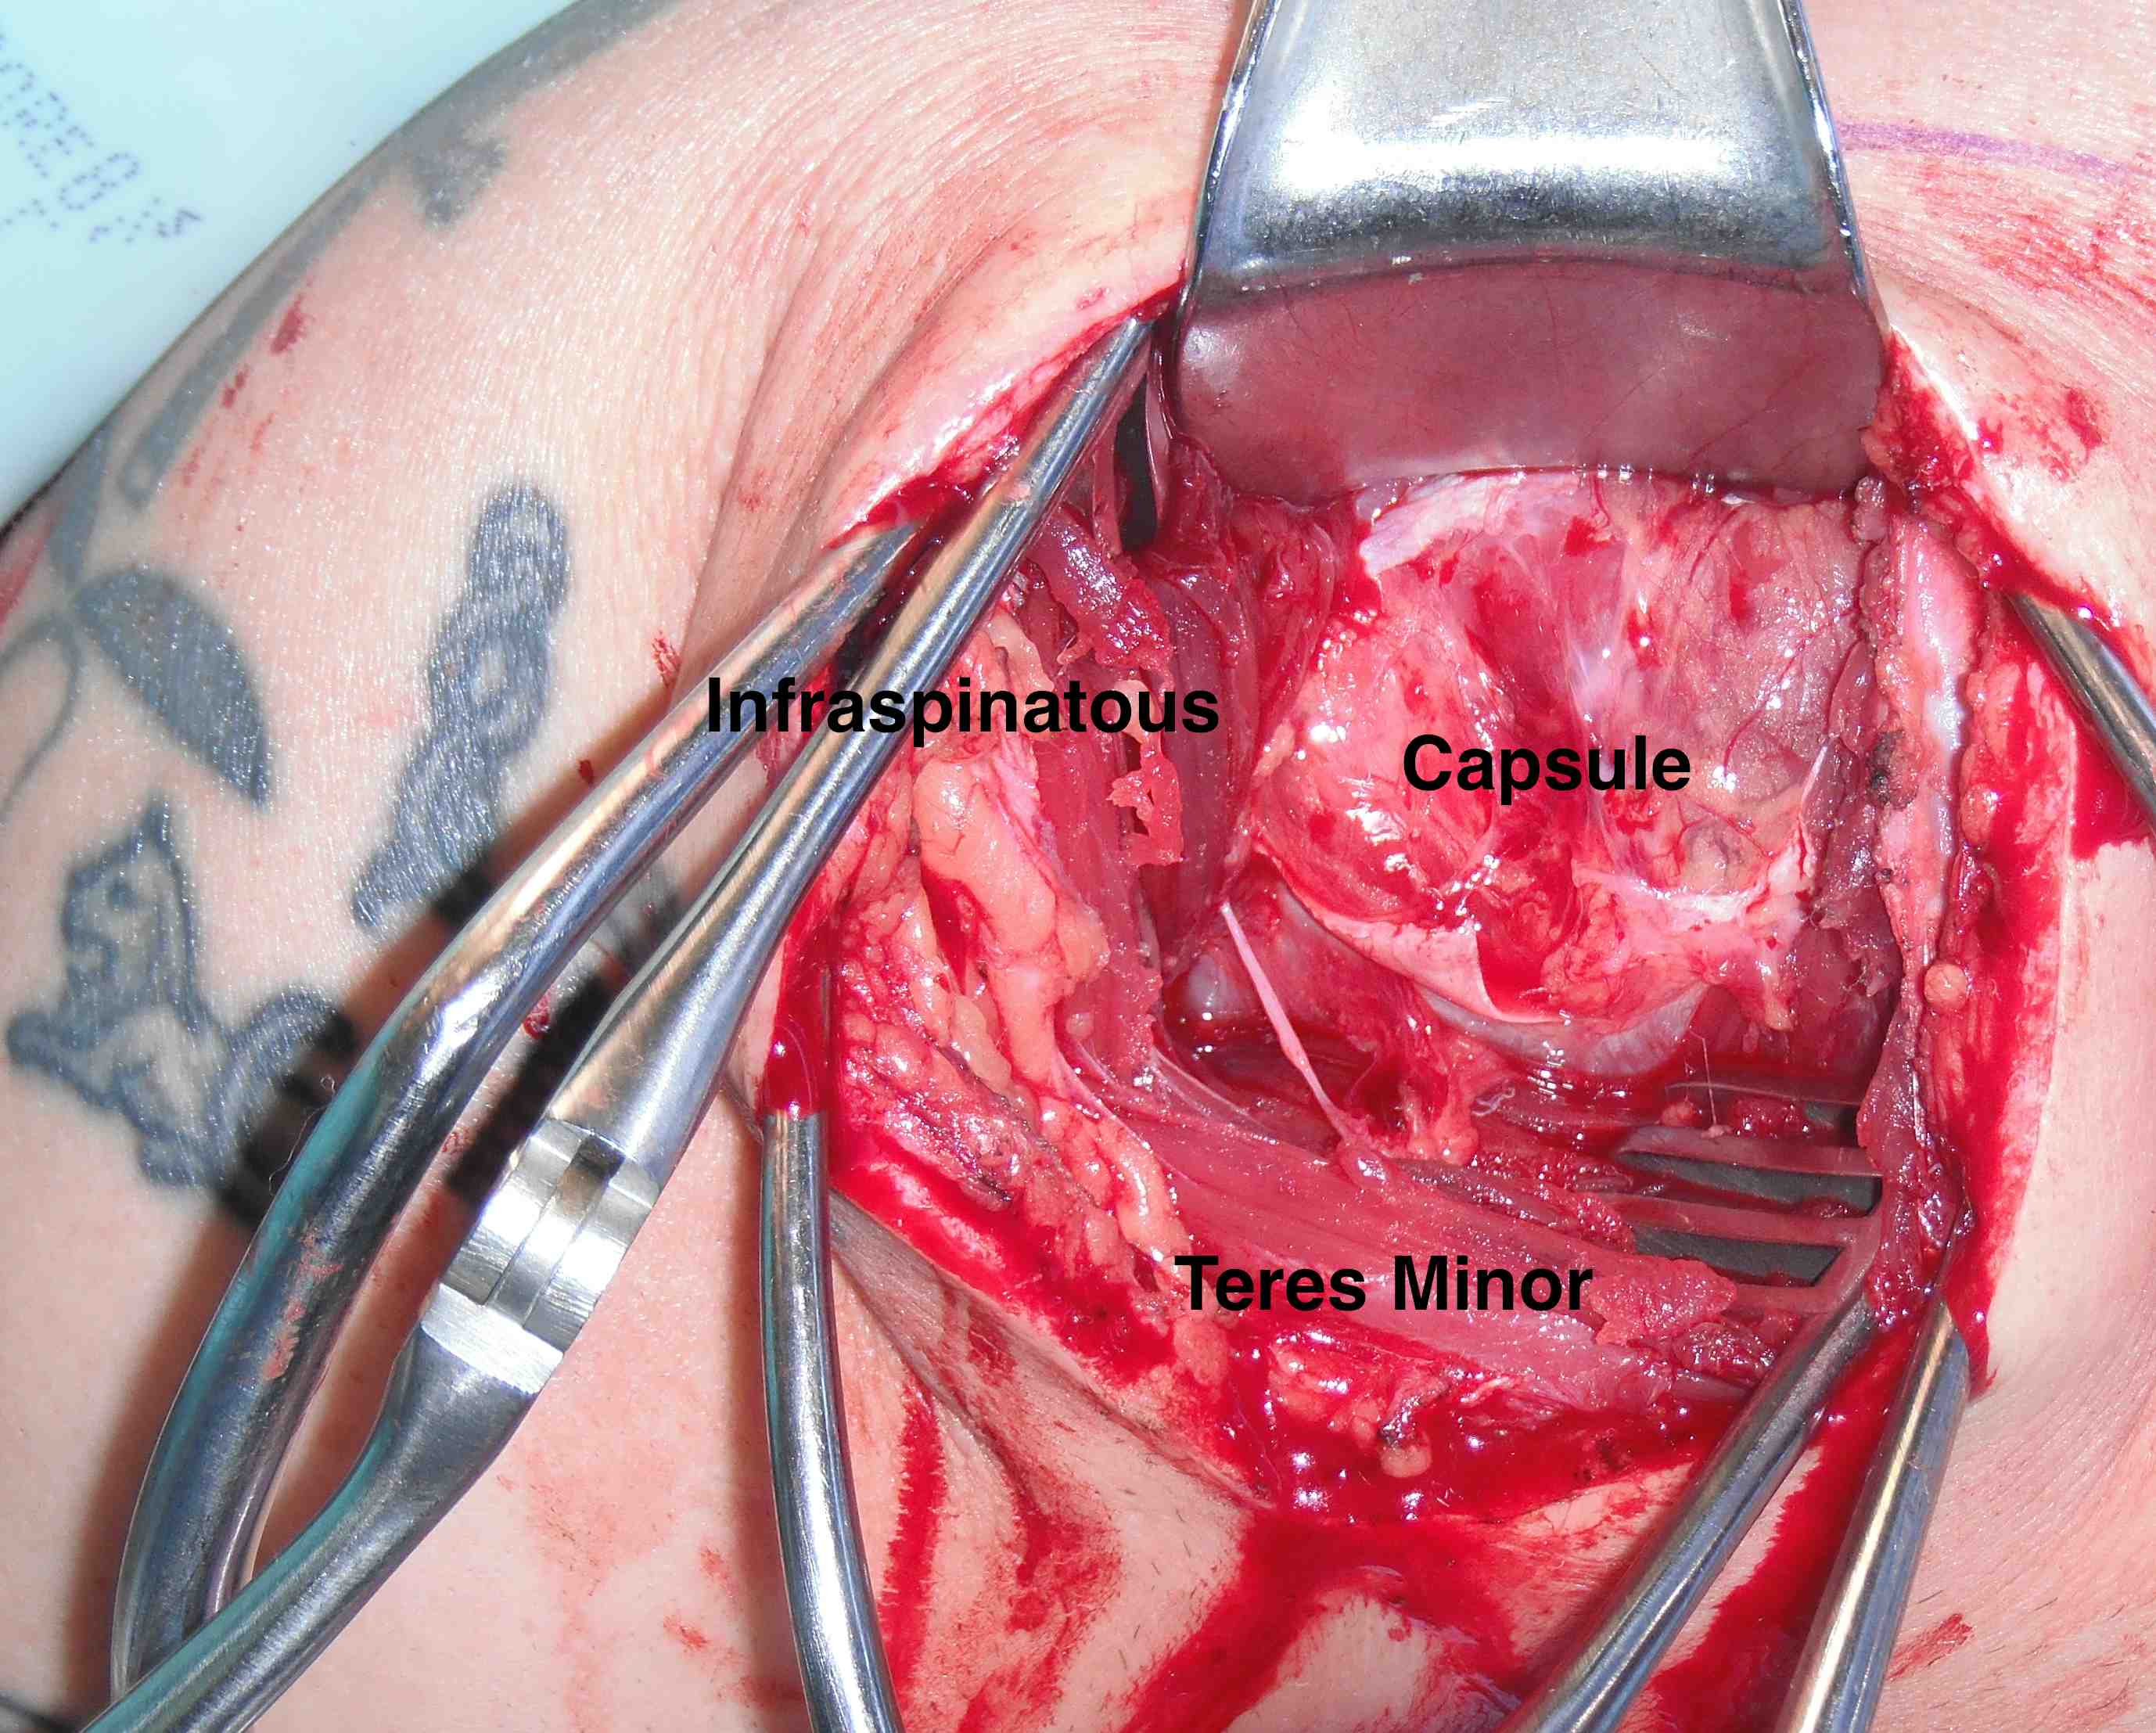

- interval: between infraspinaus and teres minor

- can detach infraspinatus tendon and elevate off capsule

- axillary nerve below teres minor

Identify interval between infraspinatus and teres minor, detach and reflect infraspinatus to expose posterior capsule and glenoid